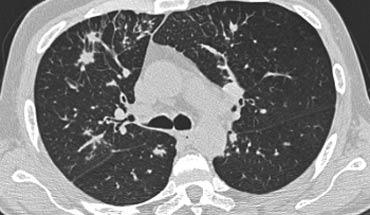

Hãy cuộn qua các hình ảnh bên trái.

Có nhiều vùng đông đặc.

Các dấu hiệu kèm theo bao gồm hạch to rốn phổi và trung thất.

Chẩn đoán phân biệt trên hình ảnh CT về cơ bản giống như trên X-quang ngực.

Kết quả mô bệnh học xác nhận sarcoidosis phế nang.

Chỉ có một gợi ý duy nhất cho chẩn đoán, đó là sự hiện diện của các nốt nhỏ có thể nhận thấy ở hình 3, nhưng rất khó quan sát.

Trường hợp này minh họa rõ ràng rằng sarcoidosis thực sự là “kẻ bắt chước vĩ đại”.